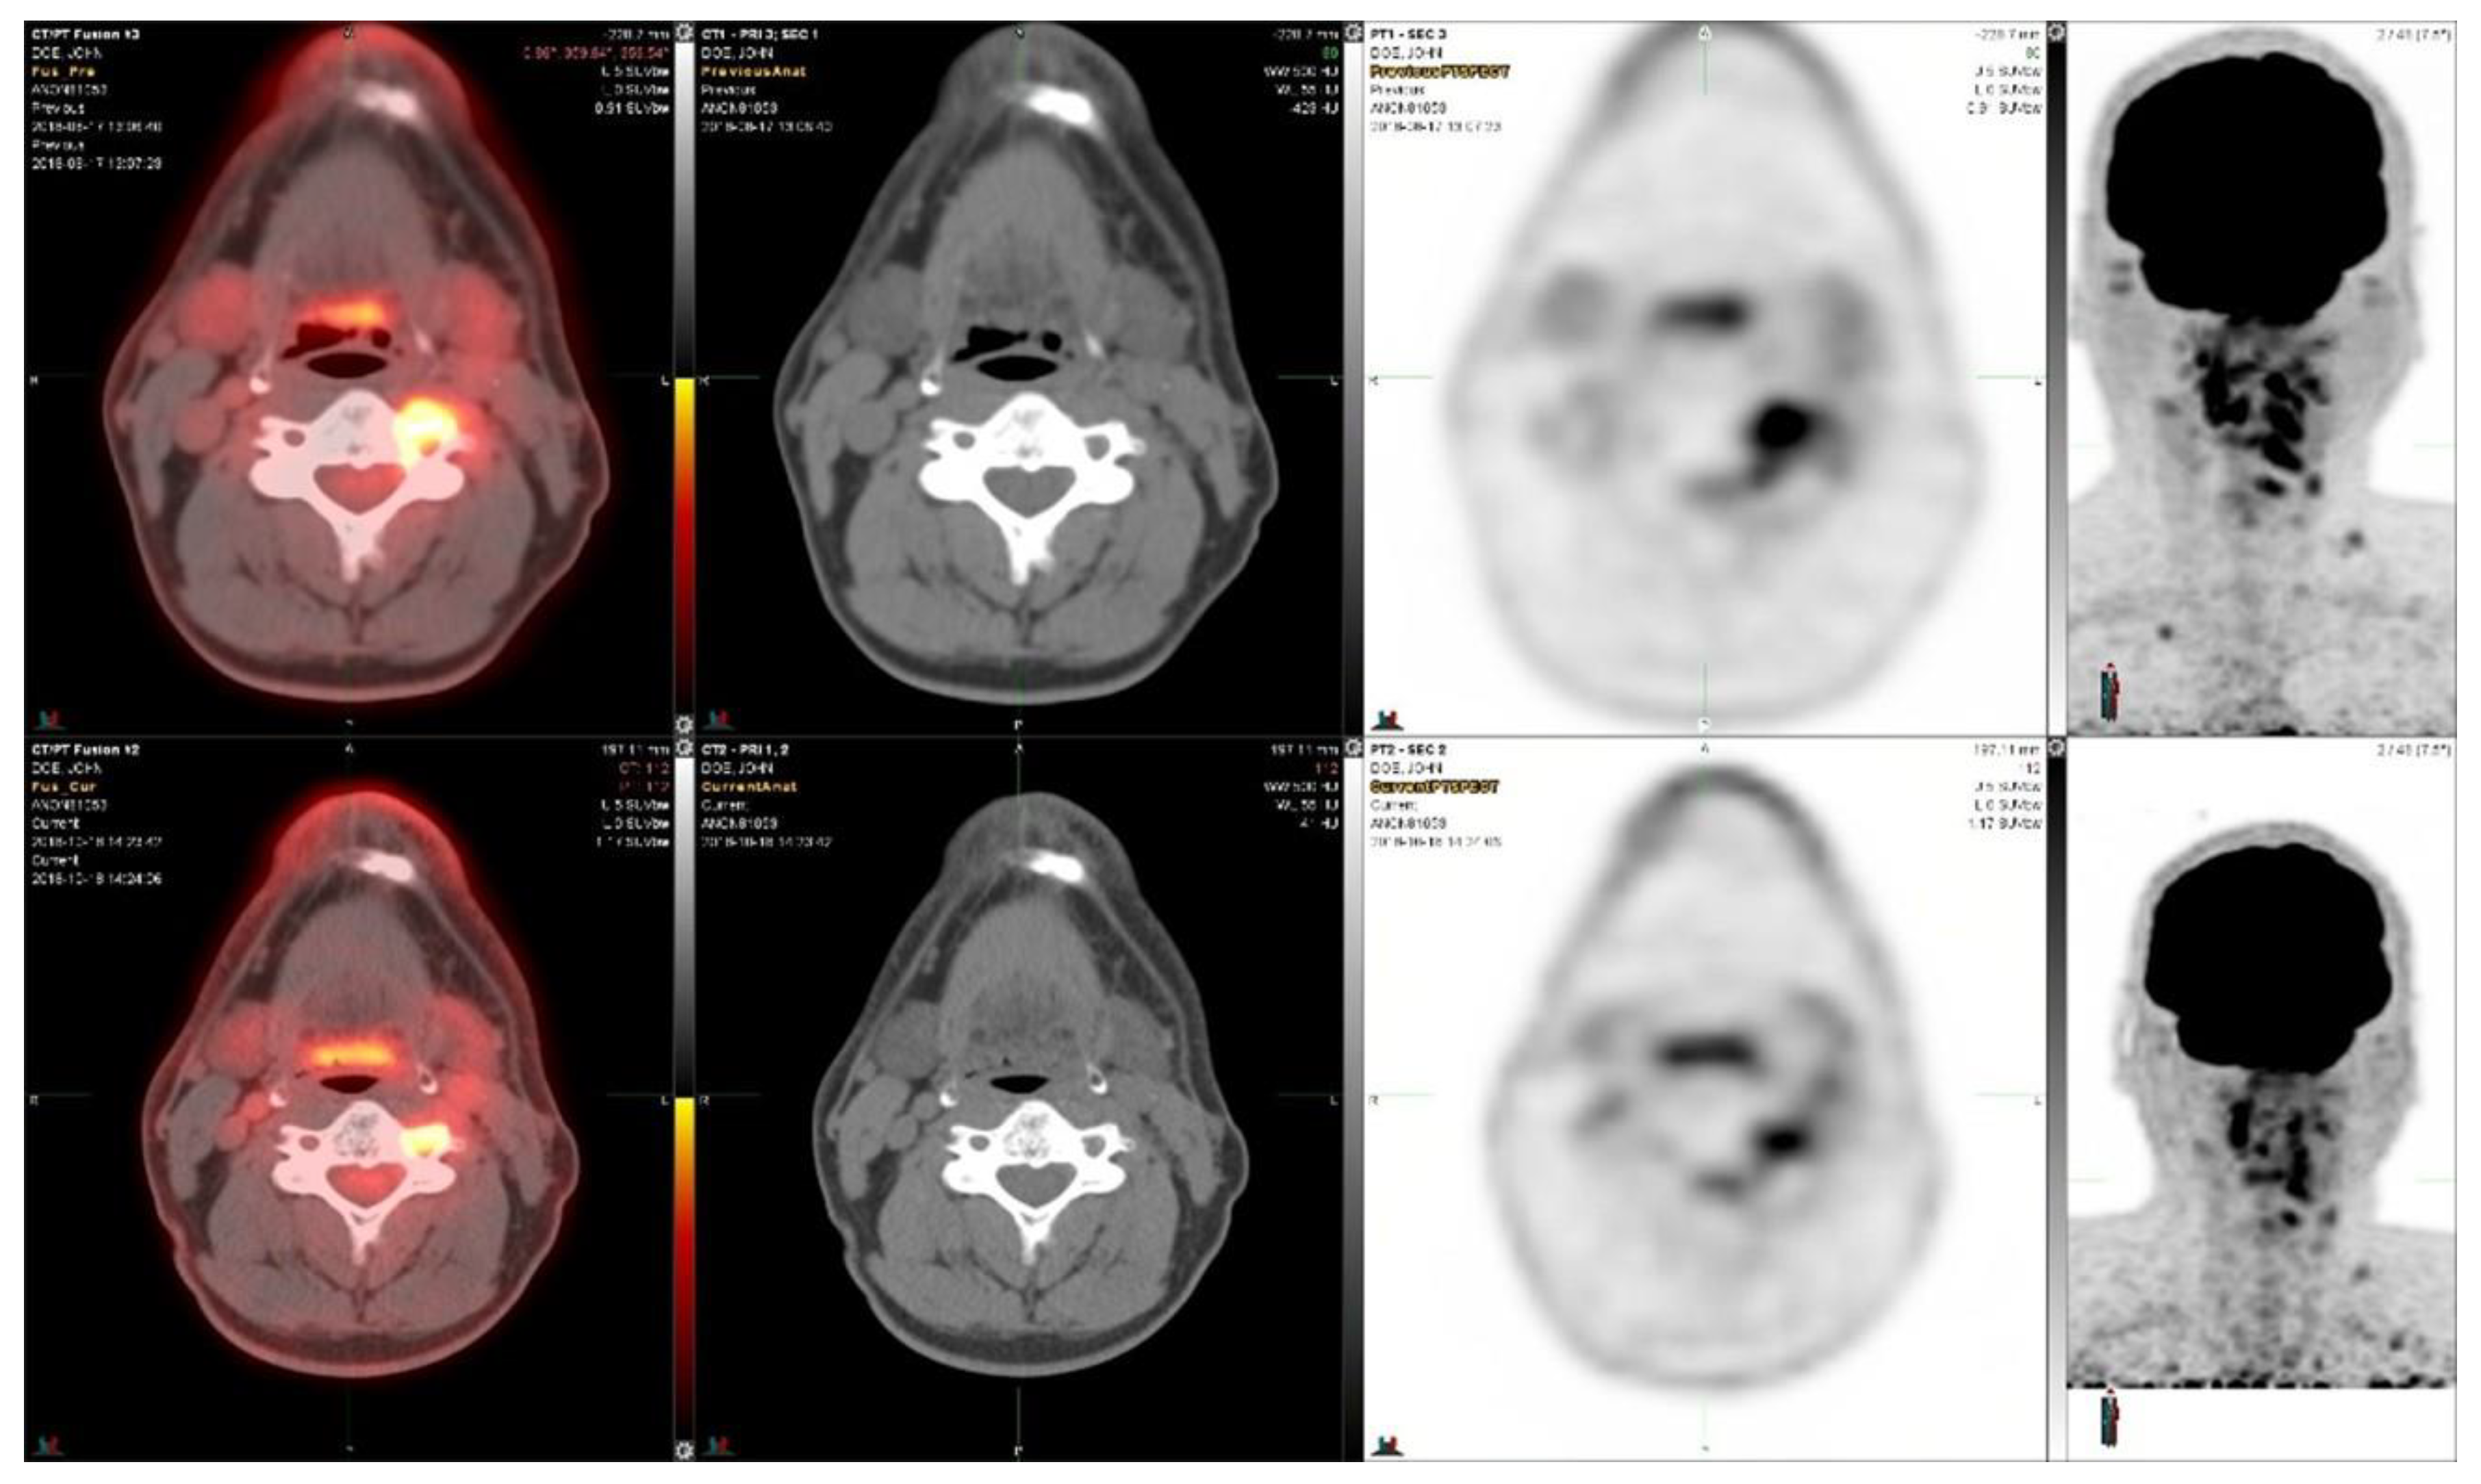

Two years later he was treated with a total dose of 45 Gy in 15 fractions using an IMRT radiotherapy technique for C2-C3 lesions in the cervical spine. He was followed for 3 years when his tumor markers started to rise. Based on his RET alteration, he was enrolled on the selpercanitib (RET inhibitor) study [3]. He received a total of 37 cycles (160 mg orally BID). Clinically, he appears to have tolerated therapy well with no significant adverse events. The response to the RET-inhibitor treatment is shown in Figure 1.

The early response this RET-inhibitor treatment in the first two months is shown in Figure 1. The SUVmax decreased from 7.9 to 6.2, i.e., −22%, in the bone metastasis shown in Figure 1. The tumor size decreased in this metastasis from 1.2 cm × 1.1 cm to 1.1 cm × 1.0 cm. The SUVmax in the largest lymph node decreased from 8.1 to 6.4, i.e., −21%, whereas the tumor size decreased in this metastasis from 1.8 cm × 1.5 cm to 1.4 cm × 1.0 cm.

Figure 1. 18F-FDG-PET/CT images from a medullary thyroid cancer patient who had an RET mutation and was treated with selpercanitib for almost five years. The upper panel demonstrates the situation before selpercanitib treatment; from the left, transaxial PET/CT fusion images, CT images, and PET images at the level of bone metastases (C2–C3), and the furthest right image shows the MIP image from the PET study on the head and neck region. The lower panel shows the situation after two cycles of selpercanitib two months later through similar images at the same level in the transaxial images and in the MIP image shown furthest to the right. In the bone metastasis, the SUVmax decreased from 7.9 to 6.2, corresponding to a 22% decrease.